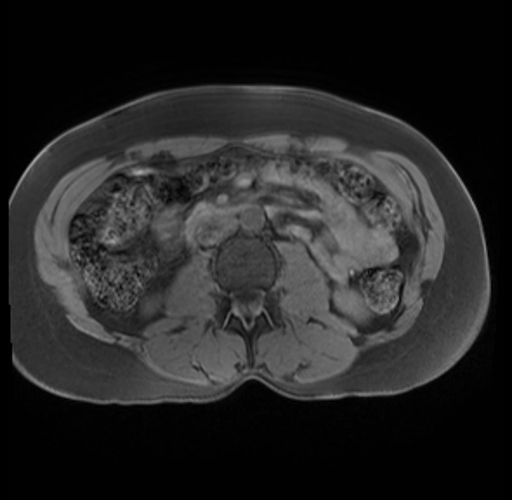

Imaging Analysis

Look through the patient's CT scan to identify any areas of concern for the necessary procedure.

Based on your CT findings, which issue(s) are present and would give reason for "planned slowing down moment(s)" in this case?